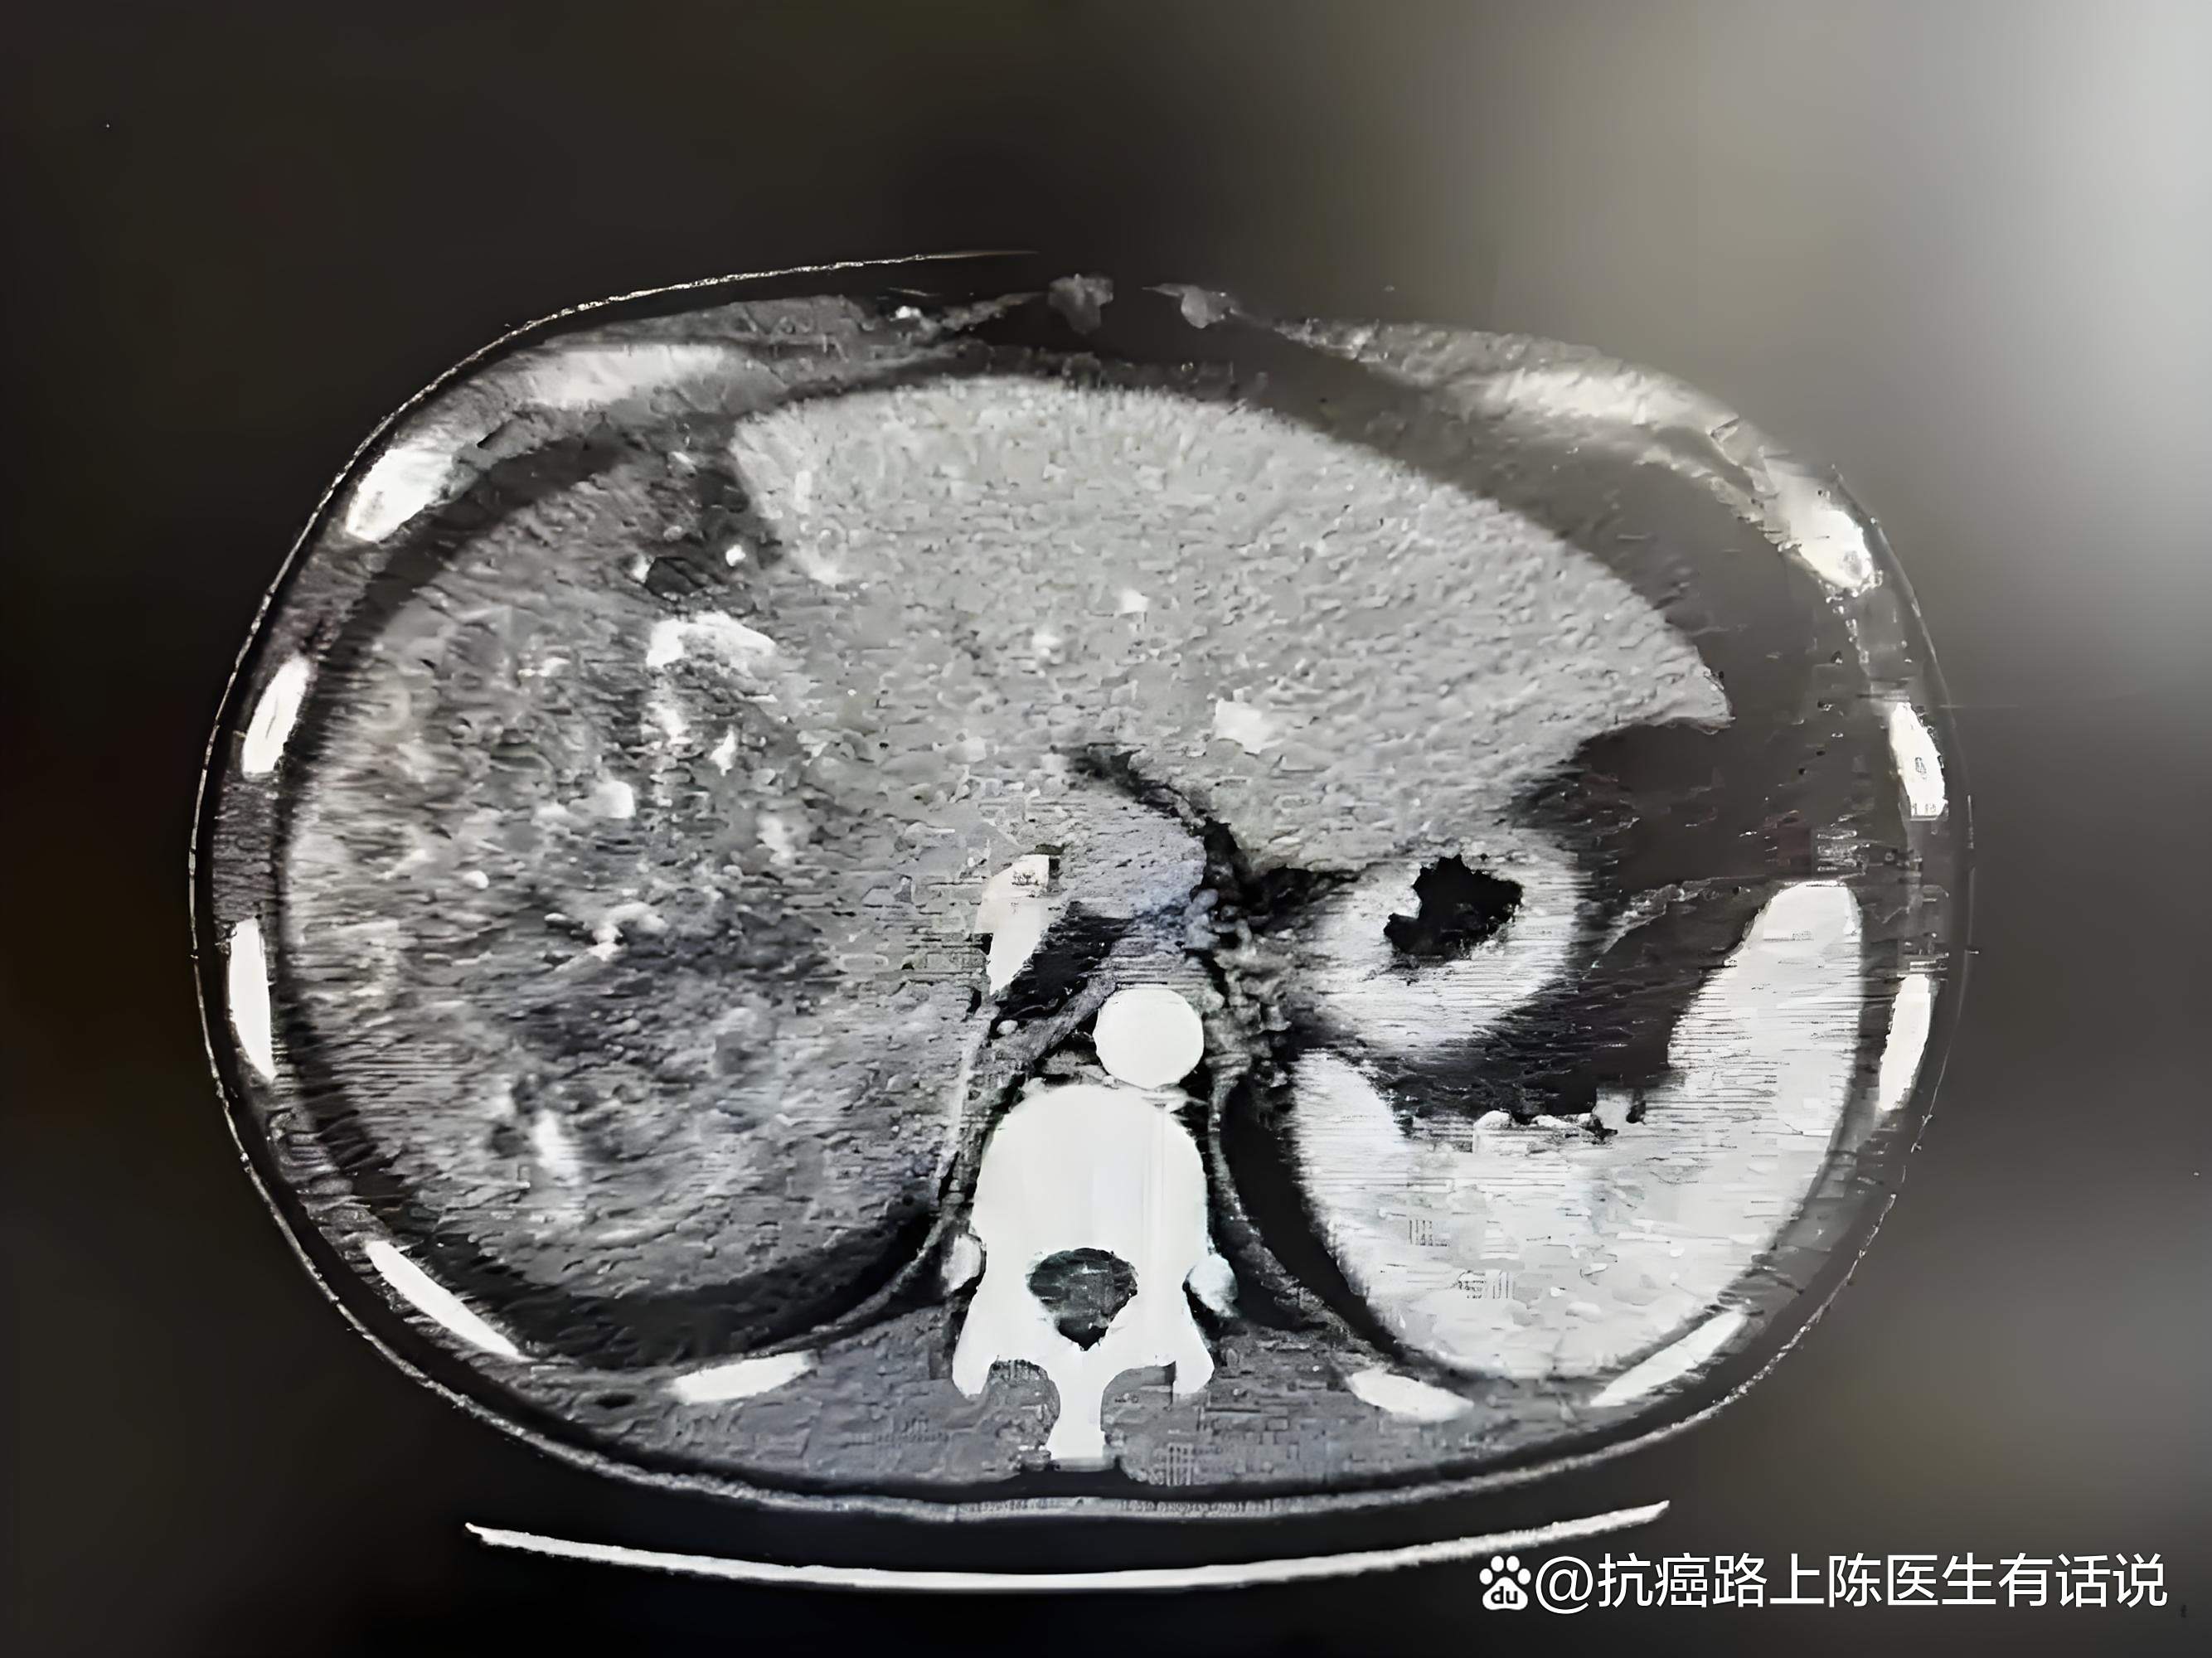

12、影像学检查增强CT或磁共振检查中,原发性肝癌动脉期明显强化,肝实质期变为低密度病灶肝内胆管细胞癌则表现为动脉期肿瘤周边可能环形强化,门脉期强化更明显,整体为乏血性肿瘤2 与转移性肝癌的鉴别 病史转移性肝癌患者往往有其他肿瘤疾病史,如胃癌结肠癌乳腺癌等 影像学检查增强CT或。